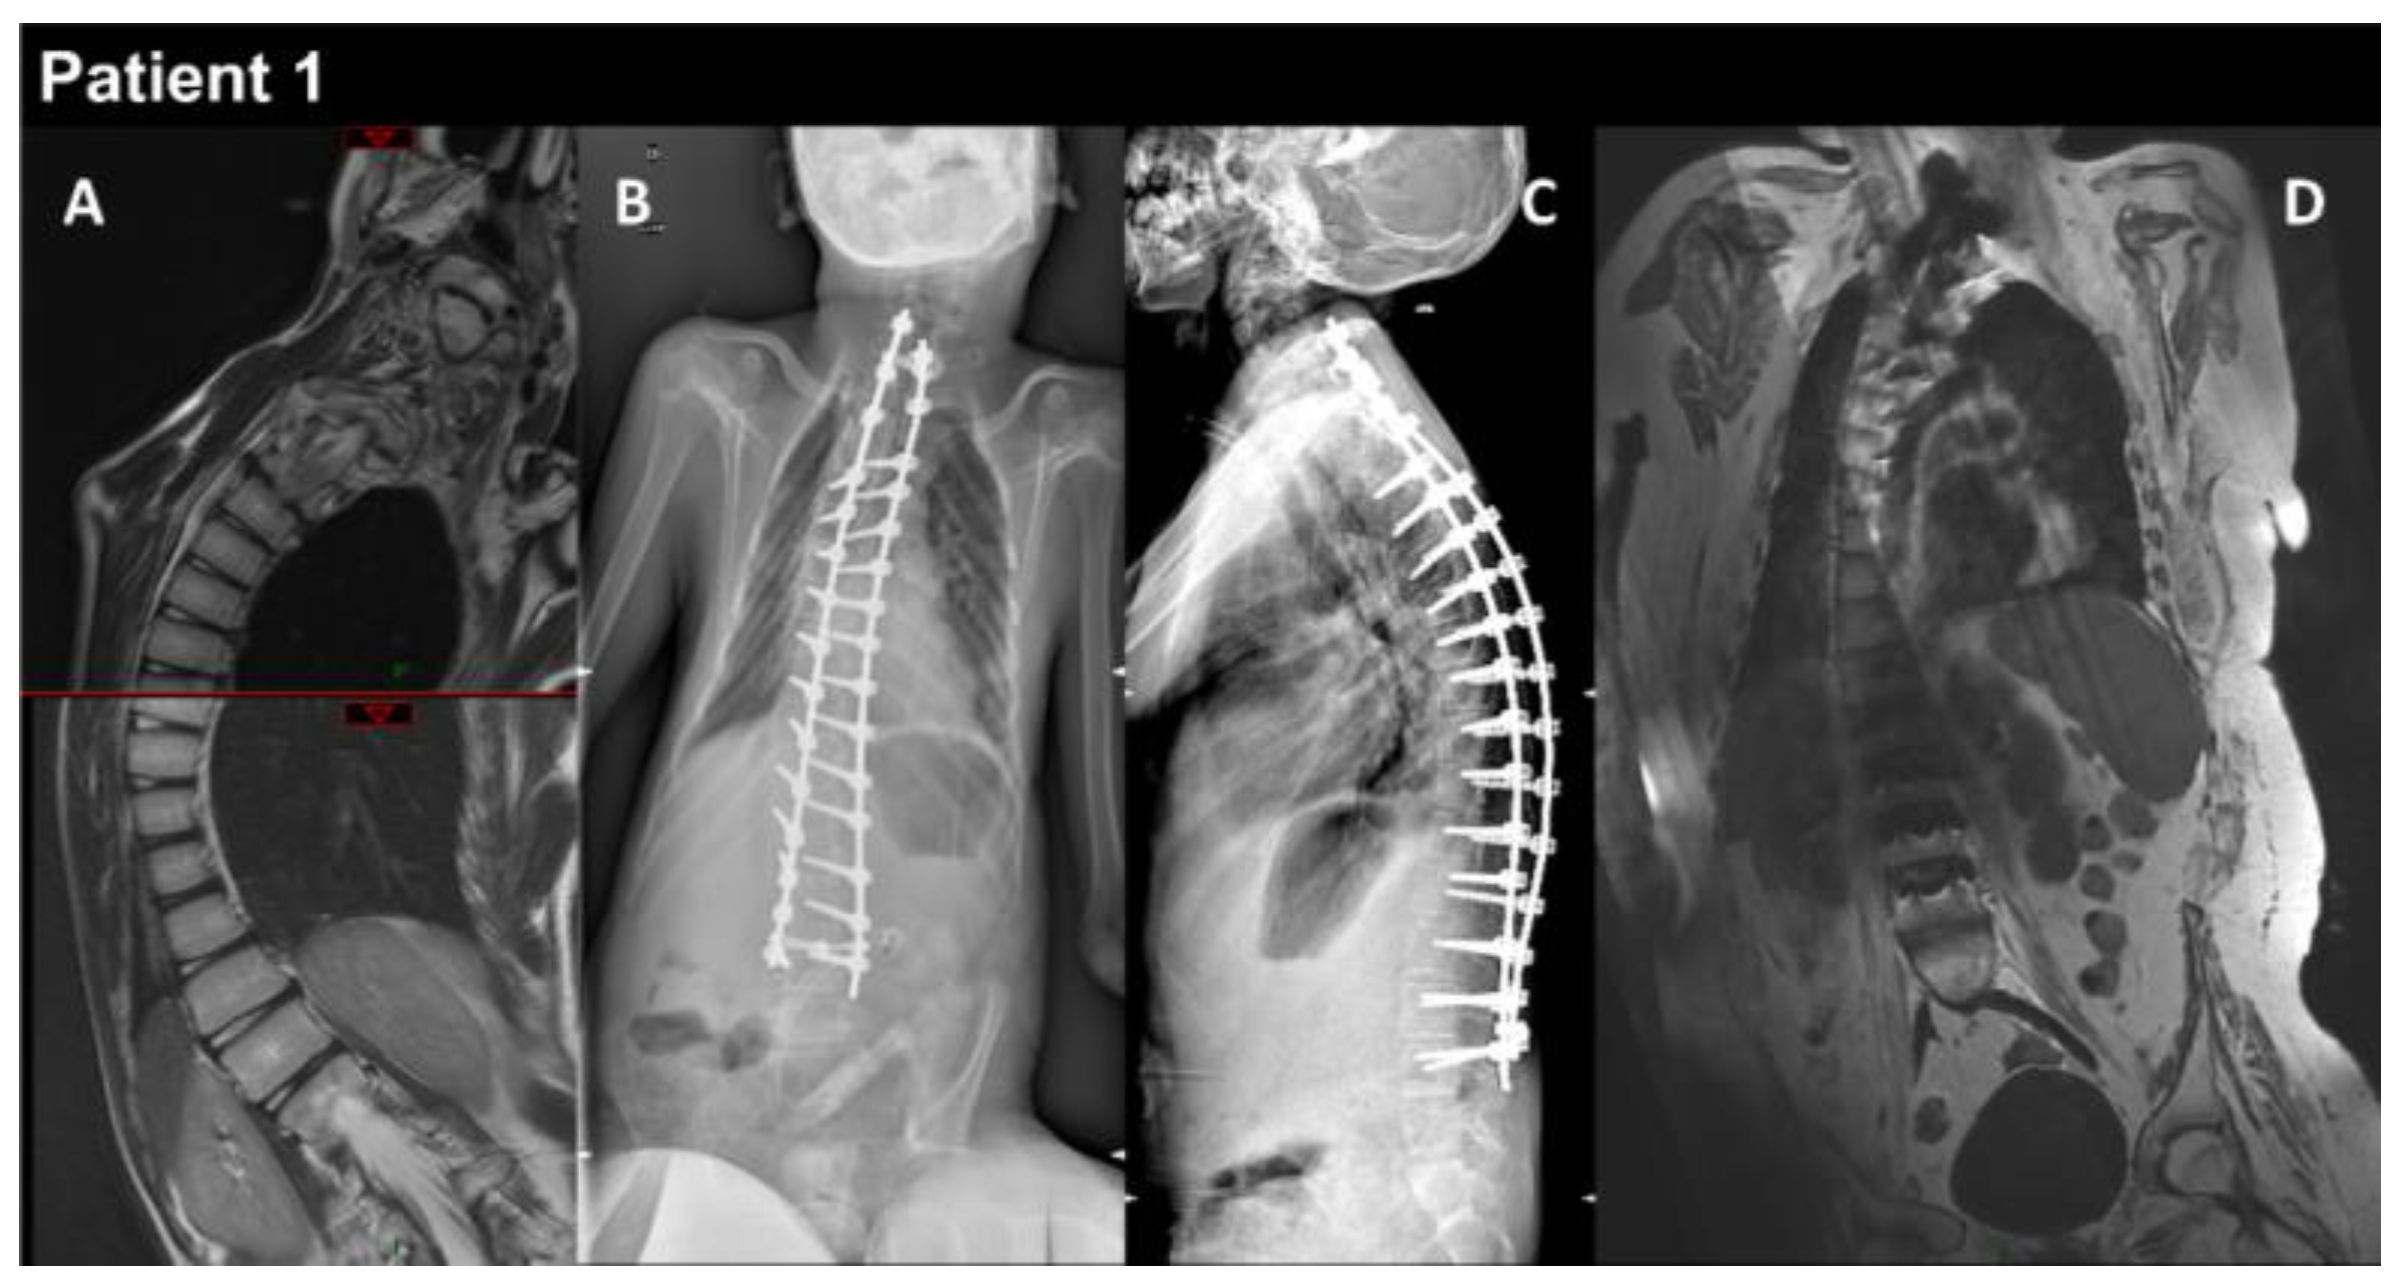

3.1. Patients’ Characteristics

| THIS STUDY | P1 | M | heteroz., de novo | RCM + myopathy | Birth | 13 y | Global | Yes | Yes | Myopathic | Normal | RCM | Restrictive respiratory syndrome | Alive at 17 y | Yes |

| P2 | M | heteroz. | HCM + myopathy | 2 y | 39 y | Global | - | Yes | - | Increased | HCM | Restrictive respiratory syndrome | Alive at 43 y | Yes | |

| P3 | F | heteroz. | HCM + myopathy | 3–4 y | 29 y | Axial and proximal | - | Yes | - | Increased | HCM | Restrictive respiratory syndrome | Alive at 34 y | Yes | |